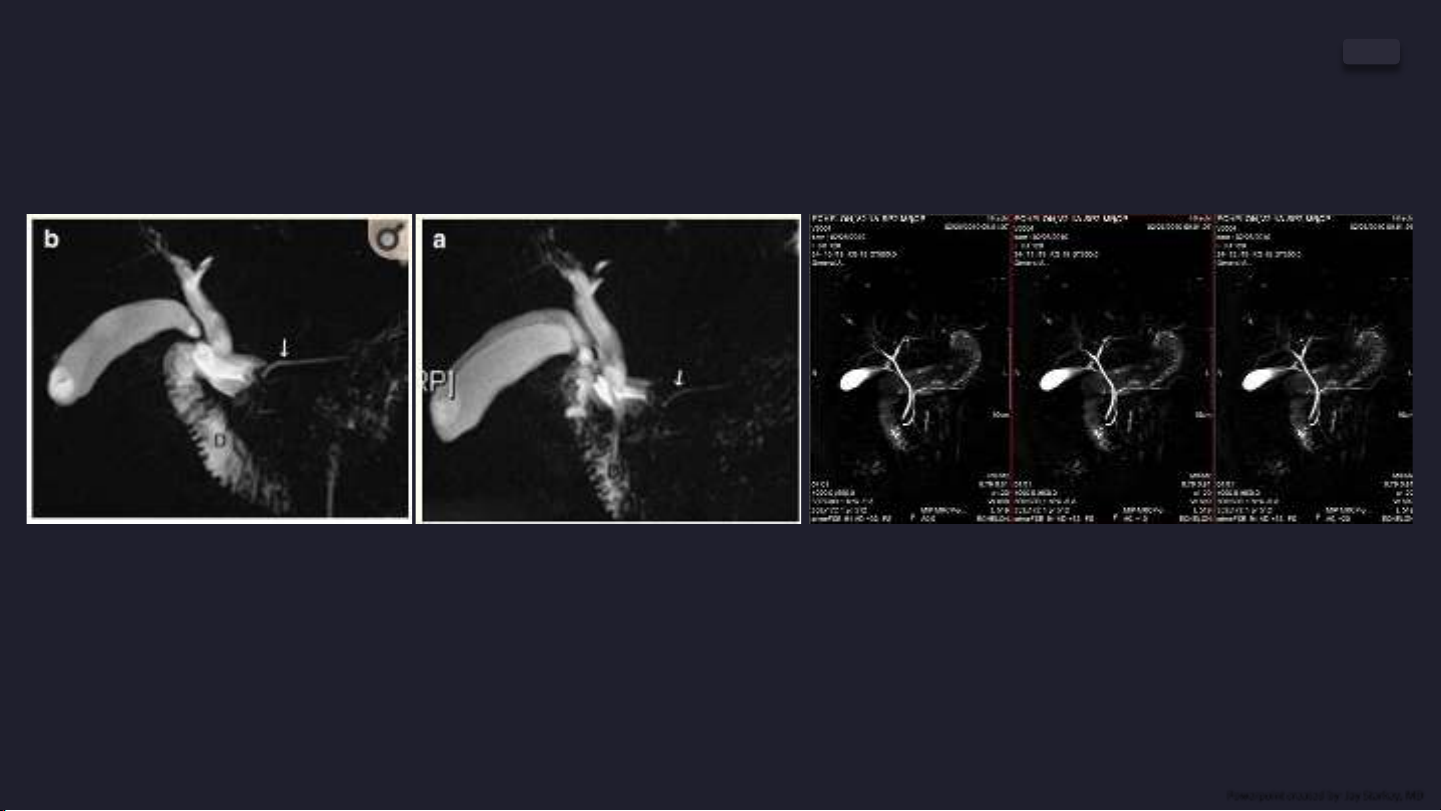

MRCP với TE=678ms trên máy

MRI SIEMENS Avanto 1.5T [1]

Hình ảnh MRCP với TE=650ms trên máy

MRI Hitachi ECHELON 1.5T

Hình ảnh MRCP trên máy